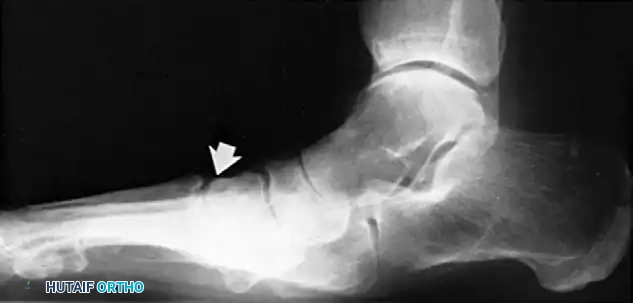

- Lateral View: Assess the medial longitudinal arch.

- Meary's Angle: The intersection of the longitudinal axis of the talus and the first metatarsal. An angle >4 degrees indicates arch collapse.

- Calcaneal Pitch: Decreased in flatfoot deformity.

Measurement of the standing lateral tibial-calcaneal angle, utilized to quantify Achilles contracture.

Preoperative and postoperative radiographic comparisons demonstrating correction of Meary's angle and talonavicular coverage following structural reconstruction.